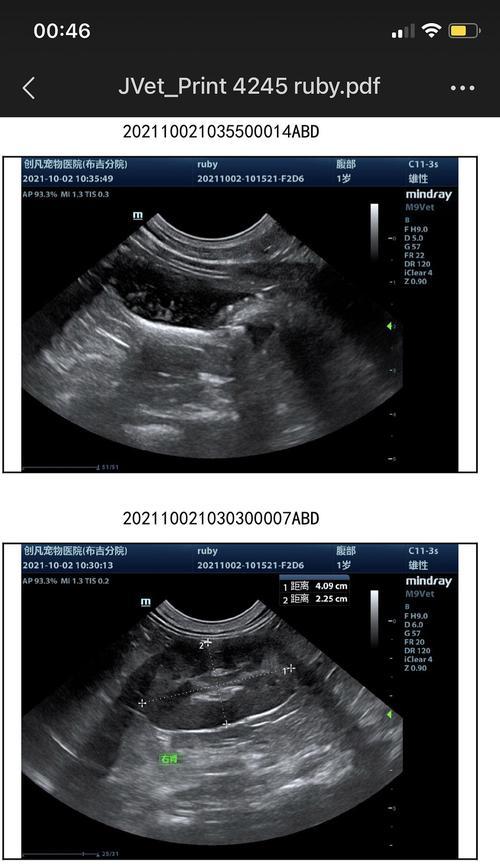

五、确诊膀胱结晶需要进行尿液分析和影像学检查

对于怀疑患有膀胱结晶的患者,医生通常会要求进行尿液分析,以确定尿液中的结晶类型和溶质浓度。此外,影像学检查如膀胱超声或CT扫描也可以帮助确认诊断。